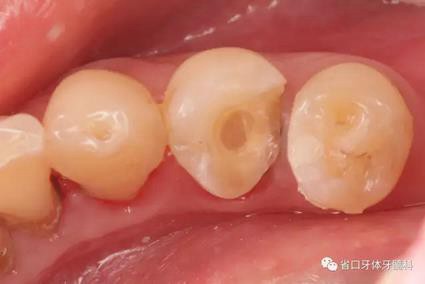

圖4:牙體預(yù)備術(shù)前照

圖5:顯微鏡下34牙體預(yù)備,拋光,35近中樹脂直接充填,選色偏白